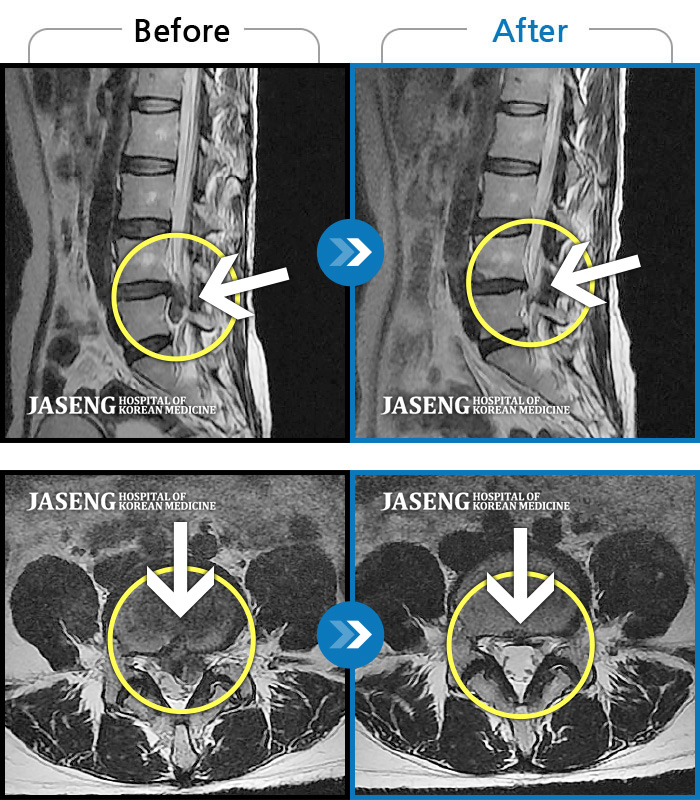

허리디스크

일산 · 배영현 원장

허리, 좌측 골반, 좌측 다리 통증 및 저림이 심해서 정상적인 일상생활이 힘든 상태

촬영시기

2021.10.04 ~ 2022.11.18

2022.12.02